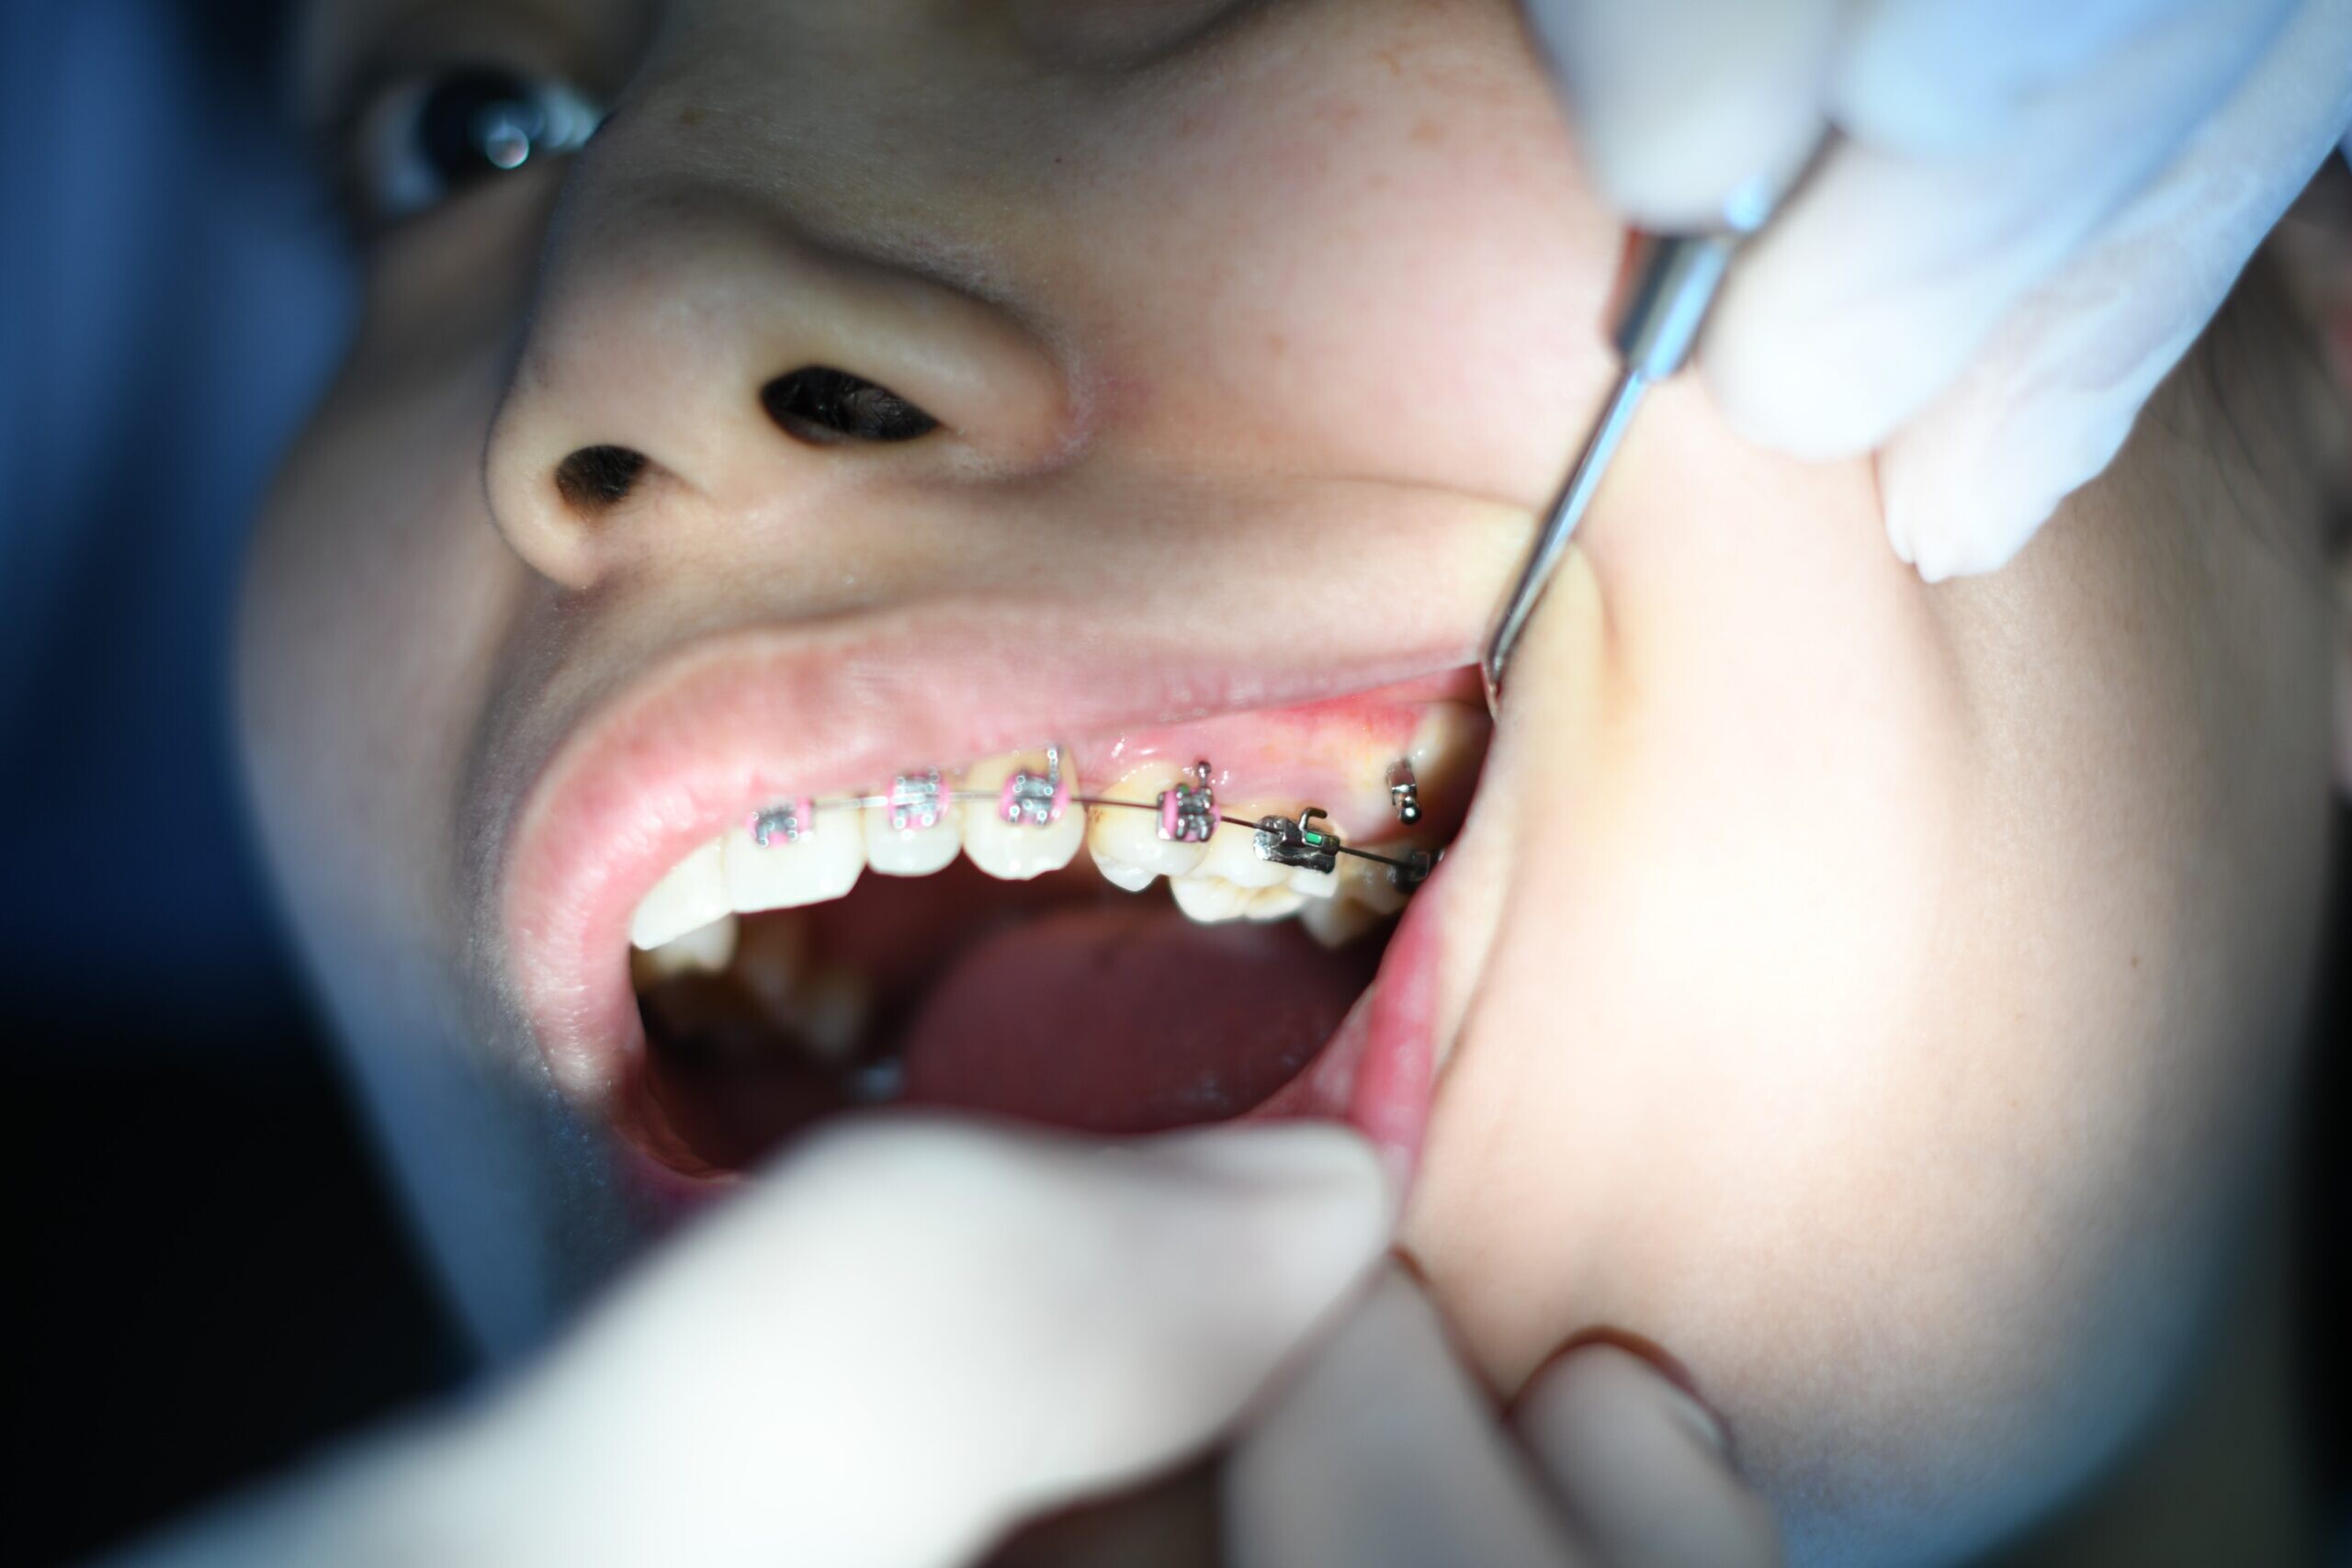

Can I Get Braces if I Have Dental Implants?

Dental implants and braces are both a great option for gaining that healthy, beautiful smile you have always dreamed of. However, these two procedures and treatments don’t go hand in hand. Dental implants act like normal teeth, but in the end, they aren’t natural teeth and that means they can be limited in some aspects, such as getting braces.